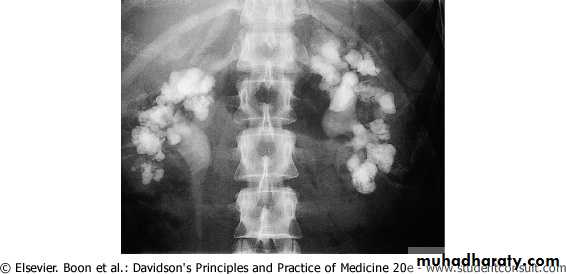

Patients with large renal stones known as Staghorn are often relatively asymptomatic.

Staghorn refers to the presence of a branched kidney stone occupying the renal pelvis and at least one calyceal system.

Such calculi usually manifest as infection and hematuria rather than as acute pain.

Bilateral staghorn calculi. The intravenous pyelogram demonstrates that, while some dye is being excreted by the right kidney, there is little function on the left.

Staghorn Calculi: struvite , calcium carbonate apatite.

cystine or uric acid,either in pure form or mixed with other components, can grow in a "staghorn“.

(but calcium oxalate or phosphate stones only rarely grow in this configuration. )

They gradually fill the renal pelvis and may extend outward through the infundibula to the calyces themselves. Very large staghorn stones can have surprisingly few symptoms and may lead to the eventual loss of kidney function.